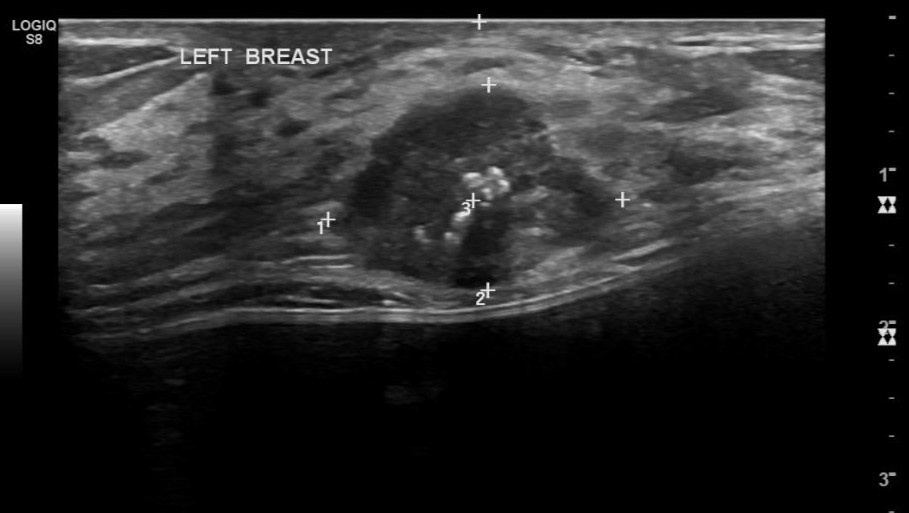

In May 2024 I found out I had the breast cancer gene (BRCA1), fought for screening and we found the lump, no biopsy was recommended (spoiler…). BRCA1 mutation = 72% breast cancer, 44% ovarian risk, recommendation: surgical removal of breast tissue and ovaries to prevent cancer. I worked that summer in Alberta in my favourite role of my career, the RPACT team. It’s a mental health response unit that bridges the gap between the health care system and police response, it was the most rewarding work. I took lots of time off traveling trying to solve medical issues, then cervical cancer was diagnosed September 2024, requiring a hysterectomy November 2024 after unclear margins. I decided to keep my ovaries; I couldn’t handle hormonal problems on top of all the mysteries I couldn’t get medical help for. I was so burnt out from all the medical issues, November was getting cold and I headed to Belize before I was medically cleared to fly. Calgary was a lonely place for me and I couldn’t go to the gym or work. After this cancer scare, I was fuelled to change my life. I went to Belize, saw an opportunity and ran with it! I felt the passion and spark ooze out of me as I designed and built the first gym at Secret Beach. I swear I felt like I had just figured out life, found my community and my purpose, until…

May 4, 2025, I had an itch on my breast and my life stopped in that moment. It felt like there was a golf ball in my breast, I didn’t need a doctor or a biopsy. I felt like my dreams were shattered as I entered survival mode, nothing else mattered. I paid for a double mastectomy in Montreal ($50,000) to shave down surgical wait times when days and weeks mattered. Surgery confirmed it, I had one of the most aggressive multiplying cancers that exists, Triple Negative, resistant to most treatments and a Ki-67 of 80% (30% is considered fast growing cancer). My compromised immune system (persistent Grade 2 lymphopenia) made chemo a challenge, so I went to Germany and received low-dose immunotherapy and a low-dose chemotherapy. I could only afford 2 treatments and a cancer vaccine before returning to Canada on fumes. Canada denied me further immunotherapy treatments, leaving me untreated since. A recent Liquid Biopsy (Sept 2025) confirms I still have active cancer in my body and that I'm responding well to treatment.